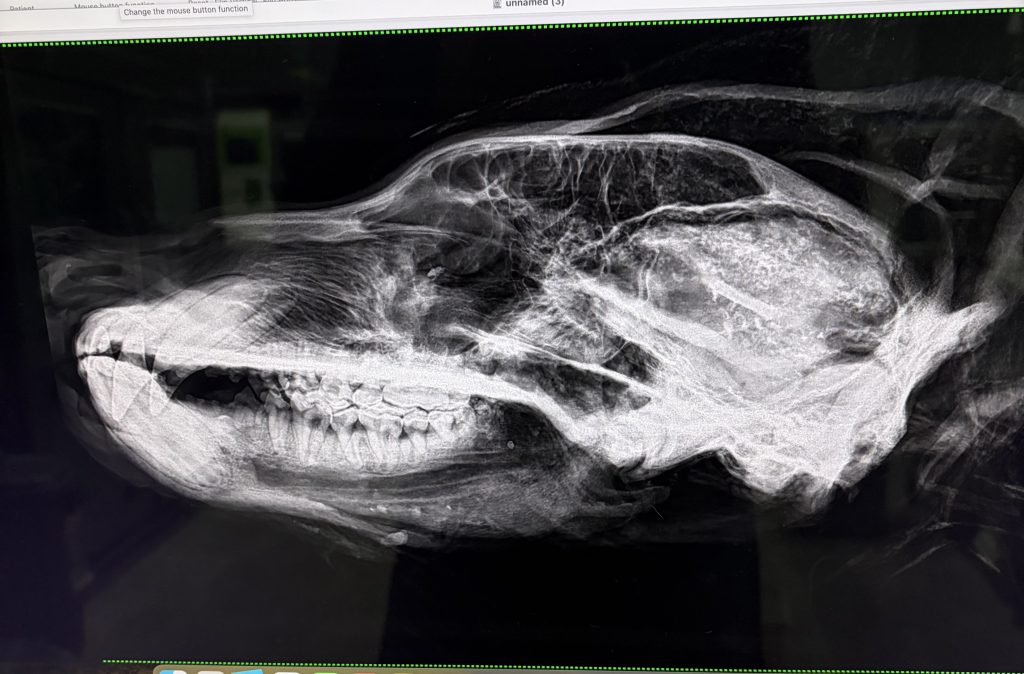

標本作る前に、骨学のために、

レントゲン検査

横と、縦から撮影

まだまだ若そうな歯をしています

歯は丈夫そう

何でも食いちぎる筋肉もあります

クマのレントゲンは初めて撮影、

初めて診たっ